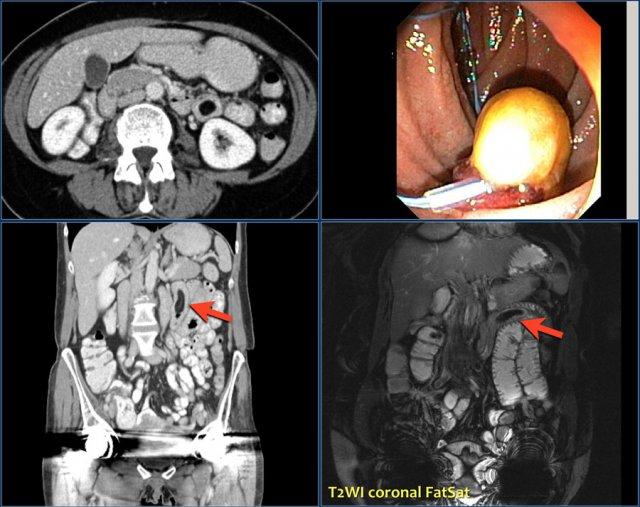

Các hình ảnh cho thấy một khối hình vòng ngắn gây tắc nghẽn ở hỗng tràng (mũi tên vàng) kèm hạch bạch huyết to (mũi tên đỏ).

Kết quả giải phẫu bệnh xác nhận là ung thư biểu mô tuyến.

Chuỗi xung T1W sau tiêm thuốc tương phản từ có fat-sat (trái) và chuỗi xung T2W (phải) cho thấy một khối gây tắc nghẽn ở hỗng tràng với bờ dạng vai (mũi tên).

Có giãn ruột trước chỗ hẹp.

Các hình ảnh phía trên cho thấy một khối hình vòng ở đoạn gần hỗng tràng có tăng hấp thu FDG (mũi tên vàng).

Các hình ảnh MRI phía dưới cho thấy cùng khối hỗng tràng đó với bờ dạng vai và hạch to mạc treo (mũi tên đỏ), phù hợp với ung thư biểu mô tuyến.